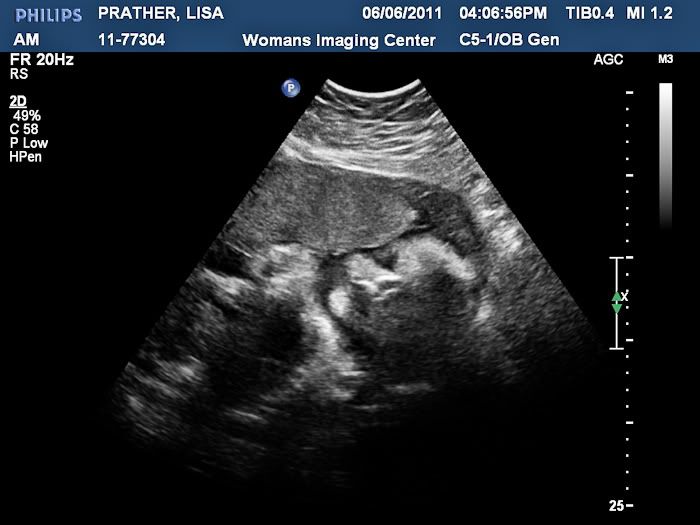

We had an ultrasound today and got to see our baby boy! It was so wonderful to see him, but even better to find out that he is still perfect. He weighs 4 pounds and 11 ounces right now!

Here is his sweet face! I cried when I saw this. I think he is just precious!

Another shot of his face:

Here is a profile shot. You can see one hand up by his face. Both hands were up by his face pretty much the whole time until the end when we decided to stretch his legs by nearly kicking himself in the face!